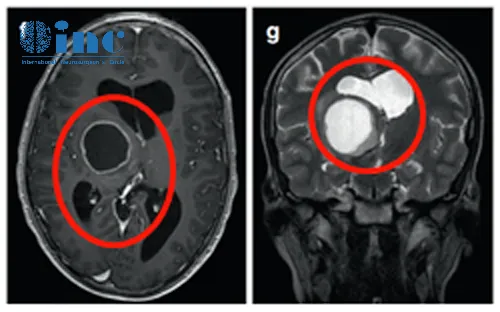

16岁男孩丘脑胶质瘤失明10年,近全切术后3年未复发

患者情况:16岁的Nico是个阳光开朗的大男孩,早在他4岁的时候,他就因丘脑肿瘤而做过左侧翼点入路切除手术,但手术并不彻底。在确诊为“丘脑毛细胞星形细胞瘤”后,他还做了两个周期的辅助化疗,但一切仿佛都无济于事。肿瘤在随后的10年多里中很快复发长大,Nico也出现了全垂体功能减退和严重的左侧视力障碍,几乎等于这只眼睛失明。

主刀医生:INC巴特朗菲教授

治疗后情况:术后患者治疗顺利,恢复平稳,患者继续进行全垂体功能减退的医学治疗。在术后3年的随访中,无出现任何其他新发的神经或认知功能障碍。现在的他坚强积极乐观,喜爱运动,他可以做很多他自己喜欢的事儿。